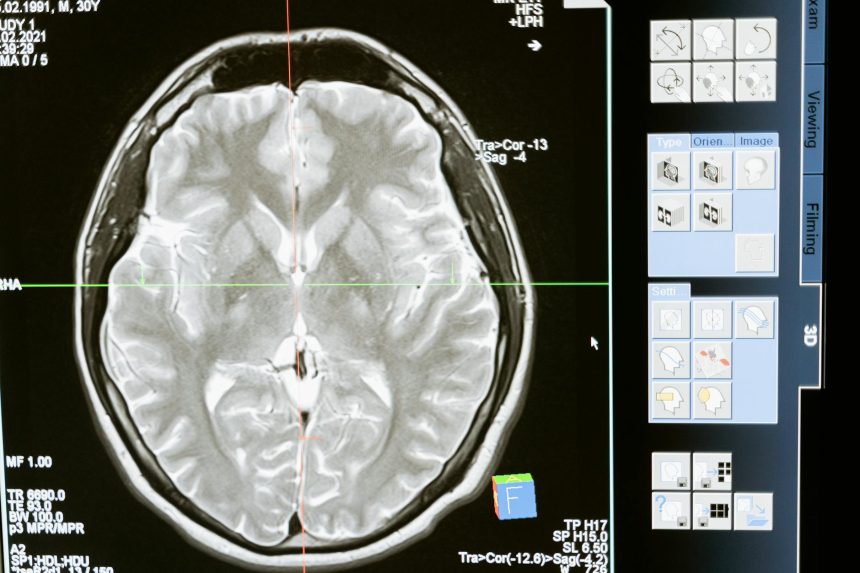

Durante um AVC, o cérebro deixa de receber oxigênio de forma adequada. Isso pode acontecer por obstrução de uma artéria ou por um sangramento interno. Independentemente da causa, o resultado é o mesmo: áreas do cérebro começam a falhar rapidamente.